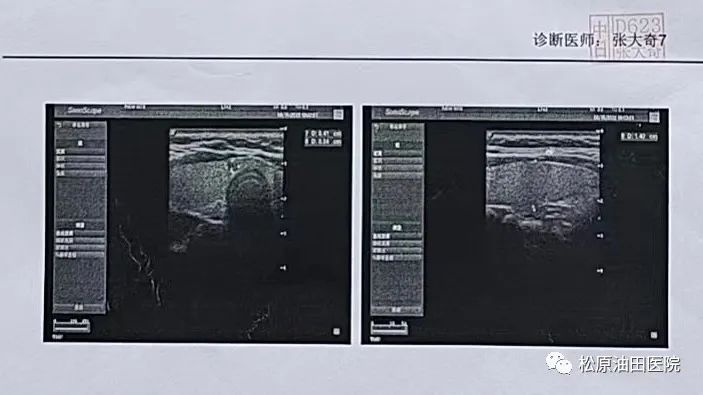

日前,松原吉林油田医院中医科的一名甲状腺结节患者通过科室引进的新疗法——中医塌渍配合中药口服治疗,结节4级,四周封包后,降至3级,大大减少癌变率,治疗效果明显。